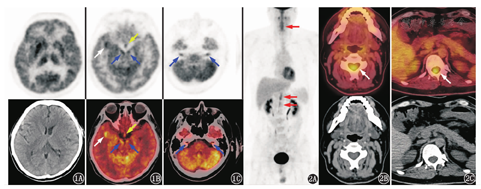

患者因颅内病变待查行18F-脱氧葡萄糖(fluorodeoxyglucose, FDG)PET/CT显像,结果示右侧颞叶前内侧、右侧岛叶、右侧壳核及尾状核头区代谢增高[最大标准摄取值(maximum standardized uptake value, SUVmax)18.3],右侧壳核及尾状核头明显肿胀,右侧侧脑室受压变窄,右侧小脑半球代谢较对侧减低;另外下丘脑、颅底多组颅神经根亦可见代谢增高,包括双侧动眼神经、三叉神经、听神经根(图1)。PET/CT躯干显像见C2~7、T11~L1水平椎管内脊髓代谢节段性增高(SUVmax 5.2),其余脏器未见明显代谢增高病灶(图2)。从定位诊断来看,听力下降定位于听神经、内侧膝状体、听辐射或颞横回;视力下降定位于视神经;肢体震颤定位于锥体外系;嗜睡定位于间脑;癫发作定位于大脑皮质;言语混乱、谵妄等精神行为异常定位于边缘系统;小便障碍定位于骶髓或马尾。患者的这些临床症状与PET/CT发现的异常代谢基本吻合。

本例患者既往有睾丸NK/T细胞淋巴瘤病史,除脊髓病变外,脑实质亦受累,还有颅底神经根、下丘脑病变,故首先考虑中枢神经系统淋巴瘤复发可能。结外NK/T细胞淋巴瘤最常见的发病部位是鼻腔,其他部位如皮肤、肠道、睾丸等也可出现,是一种发展较快、侵袭性强的淋巴瘤。中枢神经系统淋巴瘤的病理特点是肿瘤细胞在血管周围间隙内浸润生长,由于对血管壁的广泛浸润导致血-脑屏障严重破坏;肿瘤多位于脑内靠近表面或中线的部位,好发于基底节、胼胝体、丘脑和脑室周围,肿瘤可单发也可多发,密度多较均匀,边界清晰,周围轻中度水肿,水肿程度低于高级别胶质瘤和转移瘤,钙化、出血和囊变非常少见。本例颅内病变以基底节区病变为主,基底节肿胀,周围水肿不明显,这些表现亦与中枢神经系统淋巴瘤的特点相符。除脑实质受累之外,淋巴瘤还可累及神经系统的各个层面,包括脊髓、脑脊膜、神经根、周围神经,这与本例脑、脊髓、颅神经根、下丘脑等同时受累的特点亦相符。

感染性疾病同样可导致脊髓、脑代谢异常,包括病毒感染、各种细菌感染等。病毒性脑炎发病较快,早期以水肿为主要表现,CT急性期早期可表现正常或脑实质密度改变,MRI通常可见弥漫或者局限的长T1长T2信号,脑回肿胀,脑沟变浅,亚急性期以后由于血-脑屏障受损,可见斑片状强化。最常见的单纯疱疹病毒性脑炎可形成典型的"刀切"显像,即病变可从颞叶内侧面、额叶眶面延续累及扣带回、岛叶,基底节区不受累,与本例颅内病变的受累部位相反;巨细胞病毒脑炎可表现为脑室旁白质区异常信号,可累及基底节、脑干、海马等;EBV脑炎常累及基底节、丘脑,与本例的病变范围相似。病毒性脊髓炎炎性反应损伤脊髓平面以下常表现为各种功能障碍或不完全性障碍,临床表现为完全或不完全性截瘫,图3D为1例急性脊髓炎患者,其胸段脊髓代谢不均匀异常增高。本例患者既往有肺结核病史,还需鉴别中枢神经系统结核感染。中枢神经系统结核一般表现为结核性脑膜炎、颅内结核性肉芽肿、椎管内结核性蛛网膜炎,CT和MRI可发现蛛网膜炎、脑水肿、脑梗死、结核性肉芽肿等,脊髓受累时可见脊髓代谢弥漫不均匀增高,而本例颅内病变表现与结核性脑膜炎、结核性肉芽肿明显不同。

本例颅内病变还需鉴别自身免疫性脑炎的可能。自身免疫性脑炎多与作用于神经系统自身抗原的致病抗体有关,以边缘系统受累为主要表现,多为对称发生,少数为不对称受累。除边缘叶受累以外,自身免疫性脑炎还可累及基底节,表现为基底节肿胀、代谢增高;另外也可累及其他大脑皮质。本例有一侧基底节、边缘叶的代谢增高,与自身免疫性脑炎有相似之处,结合脊髓、颅底神经根等受累情况、既往淋巴瘤病史可资鉴别;另外本例患者血和脑脊液的各项抗神经抗原抗体检测均为阴性,亦不支持自身免疫性脑炎的诊断。